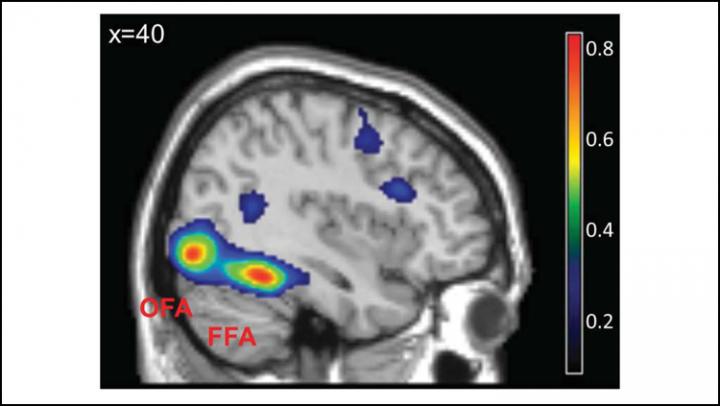

The scientists then looked at the activity of the fusiform facial area using functional magnetic resonance imaging. Seeing the same face twice in a row suppresses neural activity in this brain region. The suppression lifted when participants saw a new face --but only for white faces. In fact, with new black faces, the suppression resembled seeing the same face twice in a row. This attribute of visual processing explains the difficulty people experience distinguishing between members of an outgroup. These findings may result from life-long exposure to ingroup faces or from different motivation to process such faces.